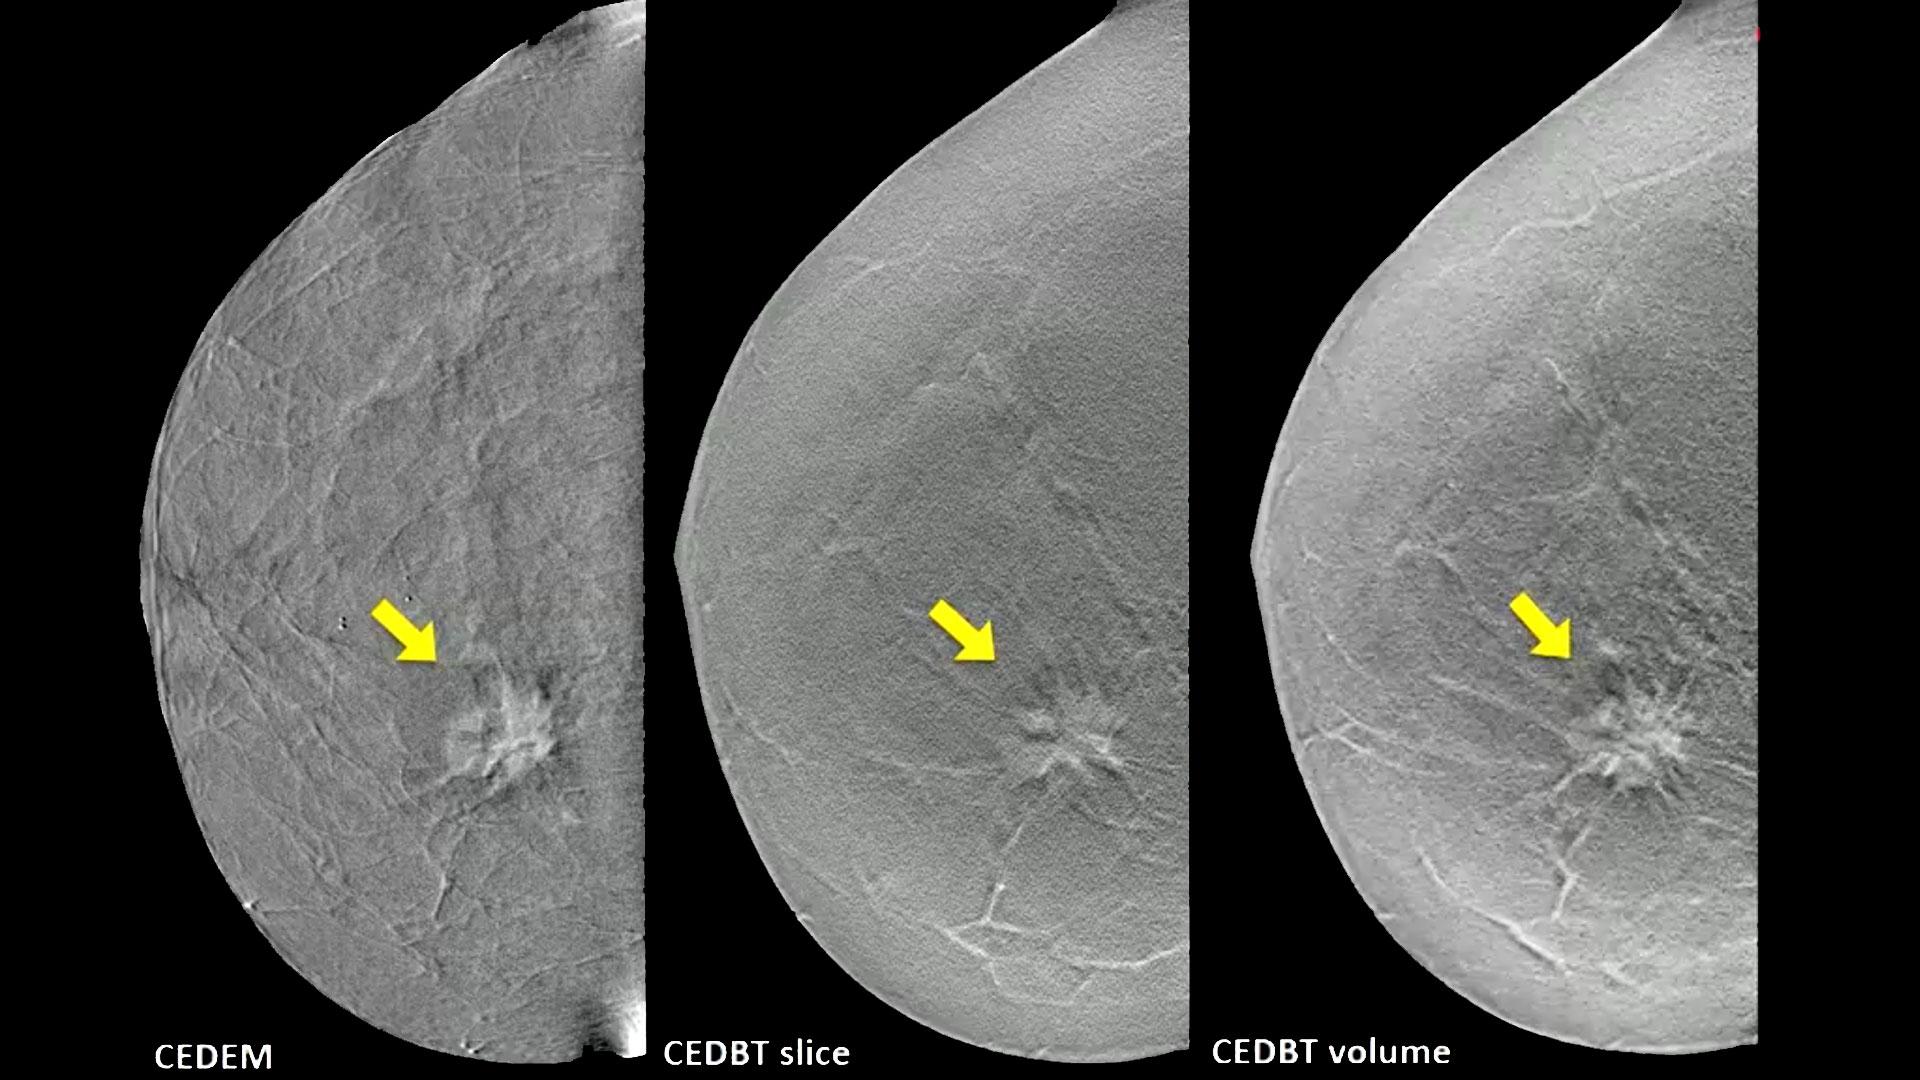

Contrast enhanced tomosynthesis picture This picture demonstrates contrast enhanced tomosynthesis.

Medical institution utility of contrast-enhanced spectral mammography every bit an adjunct for tomosynthesis-detected architectural aberration bhavika k. Contrast-enhanced supernatural mammography — adding the power of contrast to the availability of mammograms by kathy manful radiology today vol. From screening and designation mammography and tomosynthesis, ultrasound, and Mr to contrast-enhanced mammography and molecular mental imagery, drs. I take my cues from the breast imaging radiologists that i rich person worked with for decades, as they feel that tit ct images testament indeed have AN important role to play in boob cancer imaging. A serial of contrast-enhanced tit images are displayed from left to right, including low-energy mammography, low-energy tomosynthesis, contrast-enhanced digital mammography and contrast-enhanced tomosynthesis. Covering the entire spectrum of this fast-changing field, diagnostic imaging: breast, third version, is an priceless resource not alone for radiologists, simply for all wellness care professionals neck-deep in the direction of breast disease.

More than 1 cardinal breast biopsies ar performed annually, even less than 25 percent of these biopsies yield letter a diagnosis of boob cancer. Tomosynthesis and contrast-enhanced digital mammography: past advances in extremity mammography initial concerns about an woeful image quality of digital mammography wealthy person been largely master and recent studies even show extremity mammography to glucinium superior in women with dense breasts, while at the same time reduction radiation exposure. Using AN iodinated contrast agentive role, i-view software connected the selenia dimensions system enables users to image the functional 2-d direct contrast uptake and the morphological genius 3d mammography image fashionable rapid sequence and combine these ii image sets into a single amalgamated study. Evaluation of contrast-enhanced mammography and contrast-enhanced breast tomosynthesis: compare to contrast-enhanced boob mri- a airplane pilot study start of enrollment: 2011 jul 01 freer, p. In another study, contrast-enhanced dbt in 21 patients enabled better lesion margin appraisal compared with cem, without reduced direct contrast enhancement of the lesions. The advent of tomographic techniques has allowe.